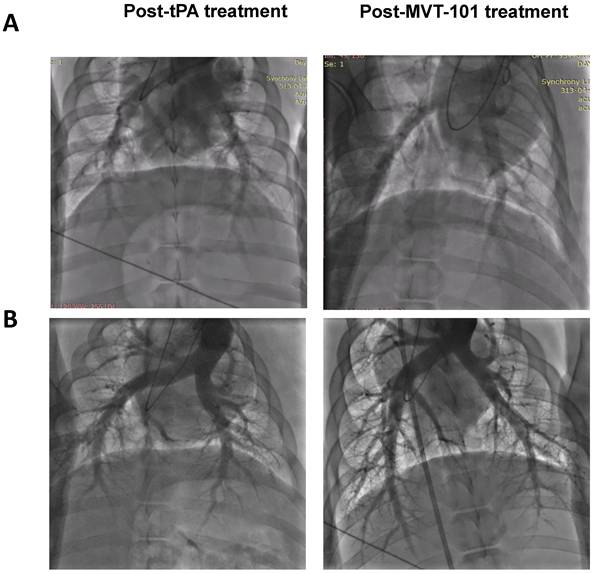

Figure 3

Pulmonary angiograms of post-tPA treatment (left) and post-MVT-101 treatment (right) with Endovascular Ultrasound (Panel A) or Transcutaneous Ultrasound (Panel B).

We measured several early safety parameters before and after sonothrombolysis treatment. Data are summarized in Table 1. The first set of pre-clinical safety data looked to understand and control the risk of pulmonary emboli via investigation of Pulmonary Artery Pressure (PAP), Pulmonary Capillary Wedge Pressure (PCWP), and Pulmonary Angiogram (PA). Angiograms are shown in Figure 3. All three endpoints can help ensure that pulmonary embolism did not result from the treatment of the DVT with MVT-101. The data collected for PAP, PCWP, and PA did not indicate significant differences between the baseline and end of study results, indicating the absence of pulmonary emboli during treatment with MVT-101. The second set of preclinical safety data looked at pulmonary function via Oxygen Saturation (sO2) and heart rate (using Pulse Oximetry). Again, no significant difference was seen between the baseline and end of study results, indicating maintained pulmonary function during treatment with MVT-101. The third set of preclinical safety data looked at the effect of treatment on hemodynamics via investigation of Mean Arterial Pressure (MAP), Systolic Pressure (SYS), and Diastolic Pressures (DIA). All three endpoints can help ensure that adequate blood flow was maintained. The preclinical safety data collected for MAP results did not indicate differences between the baseline and end of study results, indicating adequate blood flow was maintained.

The data with the EKOS™ endovascular catheter are summarized in Table 5 and data averaged are shown in Figure 2. The mean resolution of the treatment with MVT-101 alone was ~36%, higher than the tPA only condition, which was ~14 %. The highest resolution was obtained with the combination of both MVT-101 and tPA with an average resolution of ~45%. Analysis by the Kruskal-Wallis test showed that there was no significant difference between the different conditions (p value of 0.1443). Of note, EVUS + MVT-101 treatment showed efficacy without tPA while the EKOS™ catheter was not effective without tPA. There was a trend to an increase in resolution of the clot when MVT-101 was utilized alone versus tPA alone. We observed a noticeable variability in all treatment conditions using EKOS™ EVUS. Overall, most of the blood compositions summarized in Tables 7 and 8 did not show major changes. As noted for the TCUS treatment, we calculated a NLR of ~0.39 pre- and of ~1.48 post-treatment. We also observed a decrease in albumin (ALB) and total protein (TP) post-treatment as compared to baseline. Parameters and angiograms (Table 6 and Figure 3B) remained unaltered during the course of the treatment with EVUS.